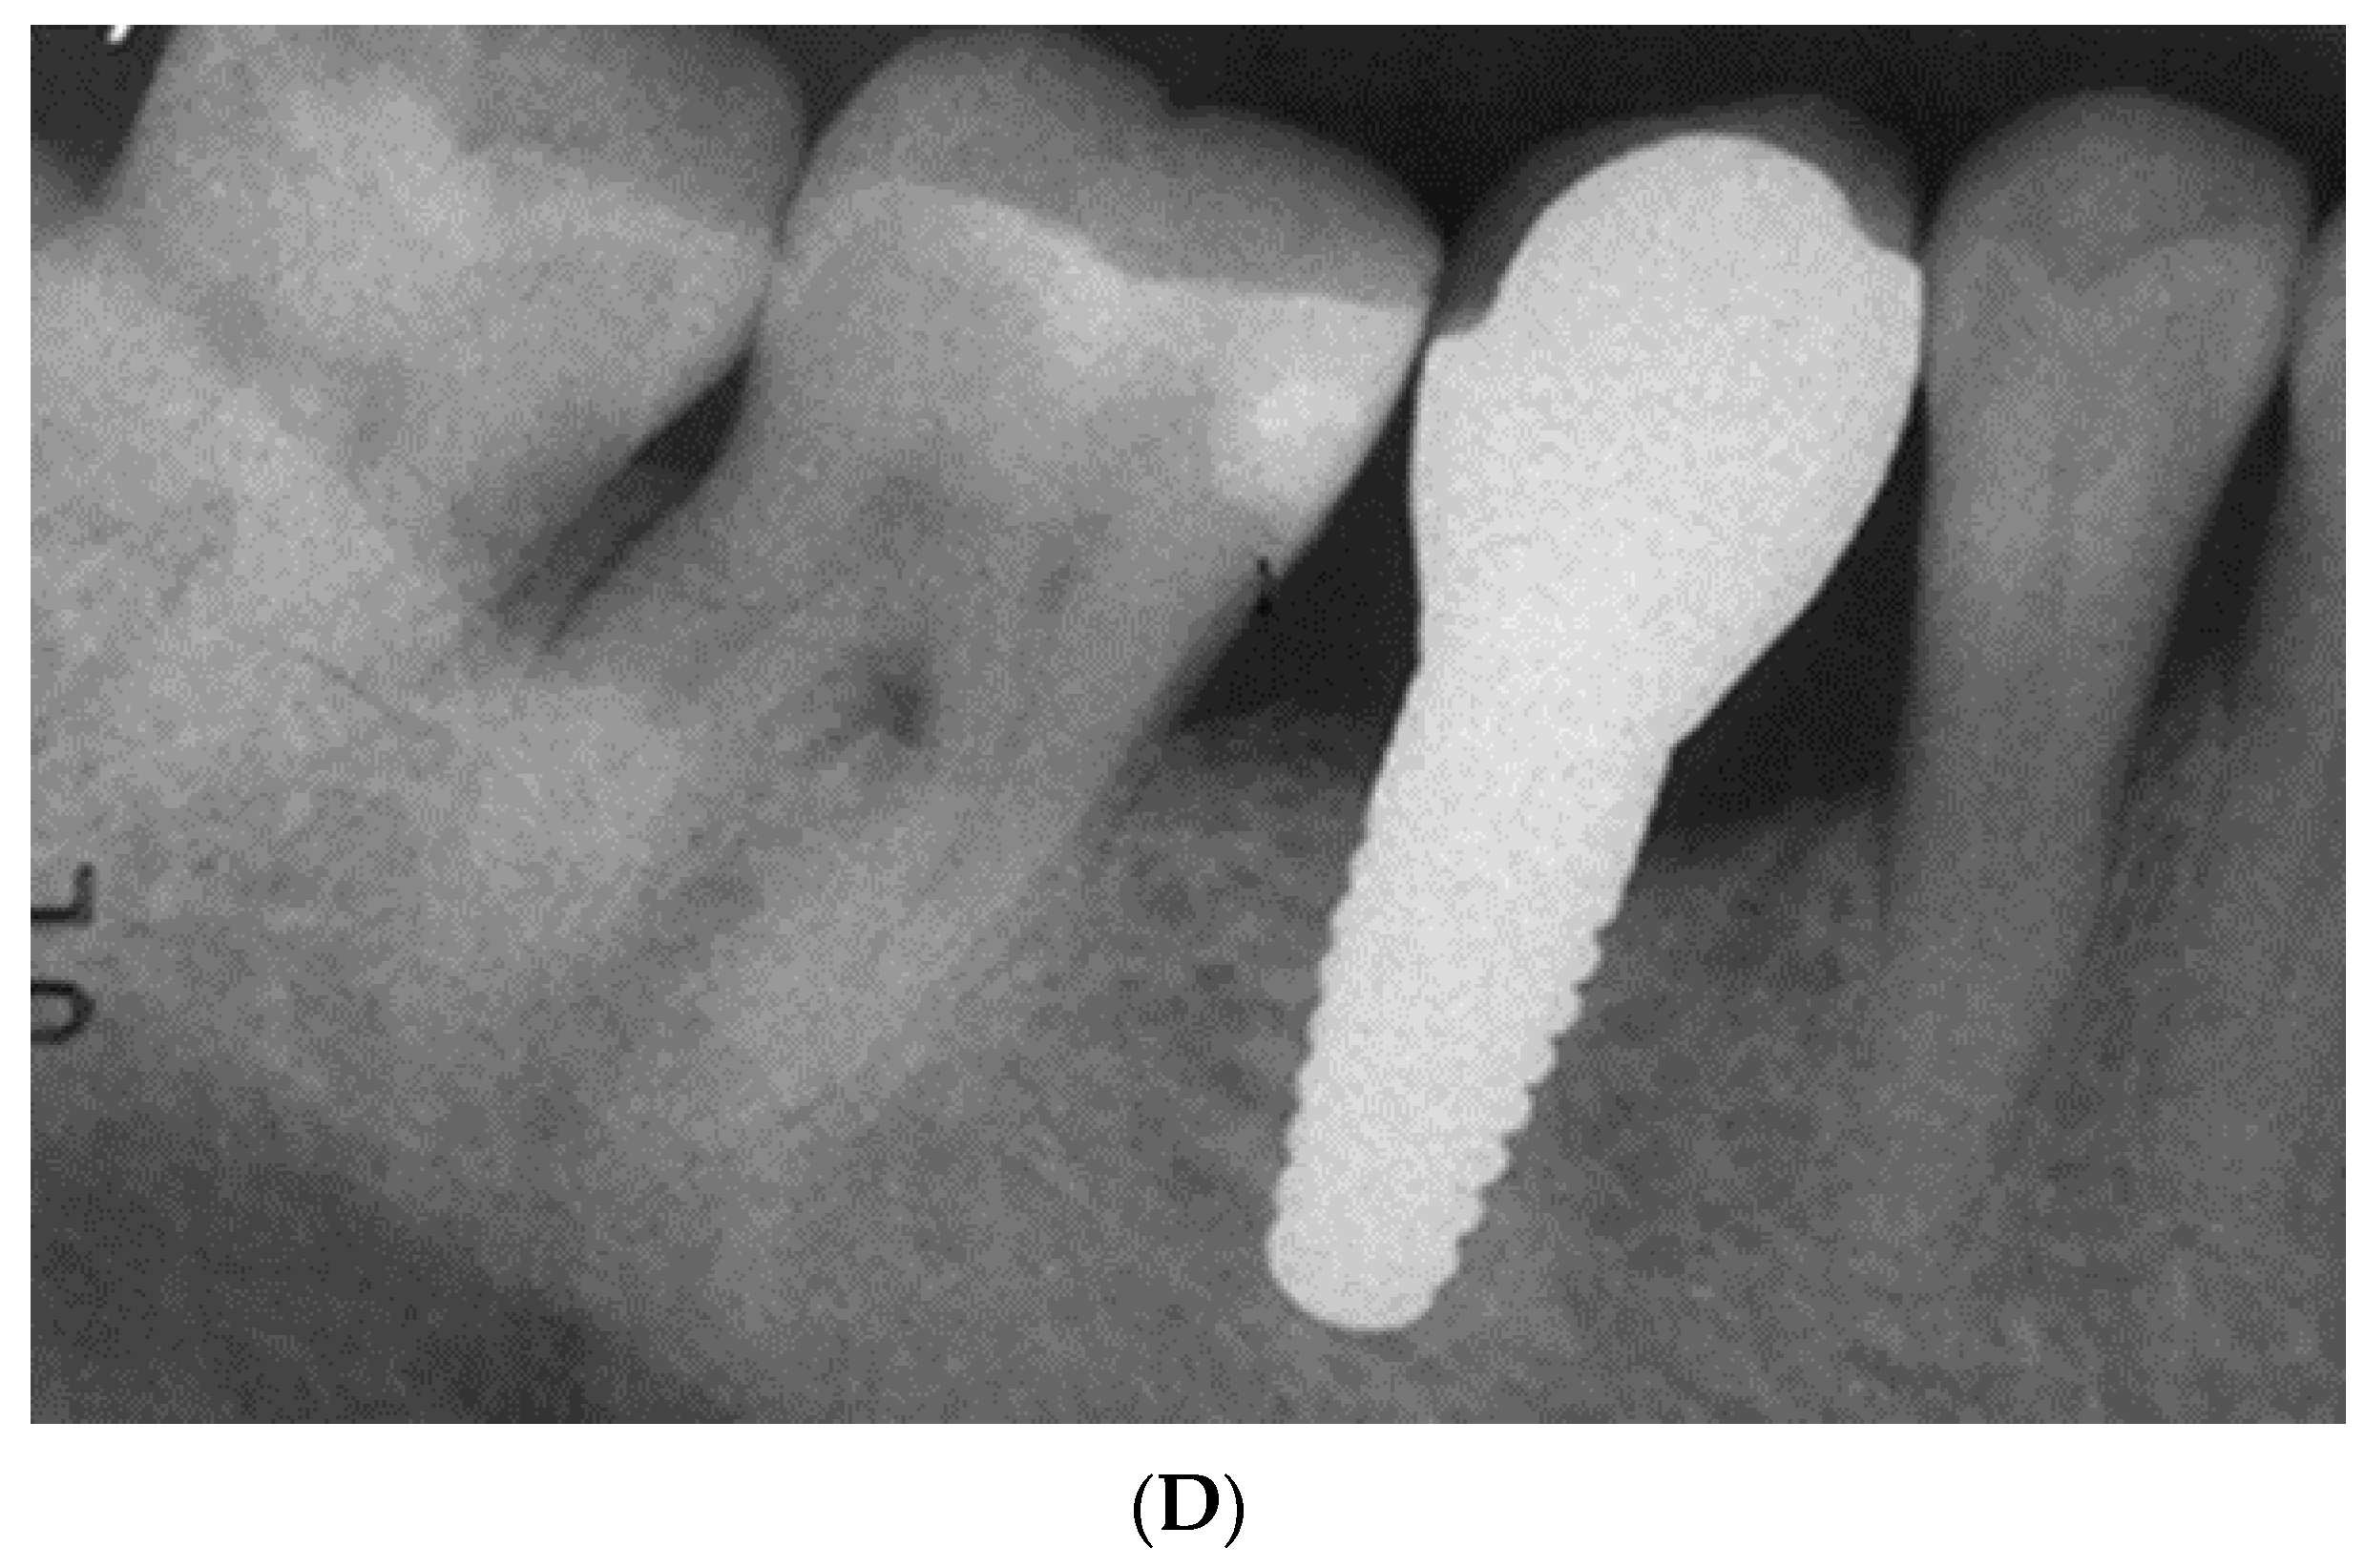

- Pirker, W.; Kocher, A. Immediate, non-submerged, root-analogue zirconia implant in single tooth replacement. Int. J. Oral Maxillofac. Surg. 2008, 37, 293–295. [Google Scholar] [CrossRef]

- Pirker, W.; Kocher, A. Immediate, non-submerged, root-analogue zirconia implants placed into single-rooted extraction sockets: 2-year follow-up of a clinical study. Int. J. Oral Maxillofac. Surg. 2009, 38, 1127–1132. [Google Scholar] [CrossRef]

- Pessanha-Andrade, M.; Sordi, M.B.; Henriques, B.; Silva, F.S.; Teughels, W.; Souza, J.C.M. Custom-made root-analogue zirconia implants: A scoping review on mechanical and biological benefits. J. Biomed. Mater. Res. B Appl. Biomater. 2018, 106, 2888–2900. [Google Scholar] [CrossRef]

- Pirker, W.; Wiedemann, D.; Lidauer, A.; Kocher, A.A. Immediate, single stage, truly anatomic zirconia implant in lower molar replacement: A case report with 2.5 years follow-up. Int. J. Oral Maxillofac. Surg. 2011, 40, 212–216. [Google Scholar] [CrossRef]

- Van Dooren, E.; Calamita, M.; Calgaro, M.; Coachman, C.; Ferencz, J.L.; Pinho, C.; Silva, N.R. Mechanical, biological and clinical aspects of zirconia implants. Eur. J. Esthet. Dent. 2012, 7, 396–417. [Google Scholar] [PubMed]

- Regish, K.M.; Sharma, D.; Prithviraj, D.R. An overview of immediate root analogue zirconia implants. J. Oral Implantol. 2013, 39, 225–233. [Google Scholar] [CrossRef] [PubMed]

- Mangano, F.G.; De Franco, M.; Caprioglio, A.; Macchi, A.; Piattelli, A.; Mangano, C. Immediate, non-submerged, root-analogue direct laser metal sintering (DLMS) implants: A 1-year prospective study on 15 patients. Lasers Med. Sci. 2014, 29, 1321–1328. [Google Scholar] [CrossRef]

- Akkoyun, E.F.; Demirbas, A.E.; Gumus, H.O.; Alkan, B.A.; Alkan, A. Custom-made root analog immediate dental implants: A prospective clinical study with 1-year follow-up. Int. J. Oral Maxillofac. Implants 2022, 37, 1223–1231. [Google Scholar] [CrossRef]